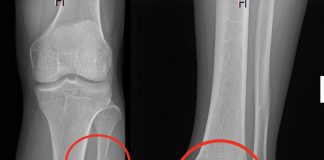

Maisonneuve Kırığı

Ayak bileği kırıklarının özel bir tipi olan Maisonneuve kırığı (MK), distal tibiofibular sindesmozun ve interosseöz membranın yırtılmasıyla ilişkili olarak fibulanın proksimal üçte birinde meydana...